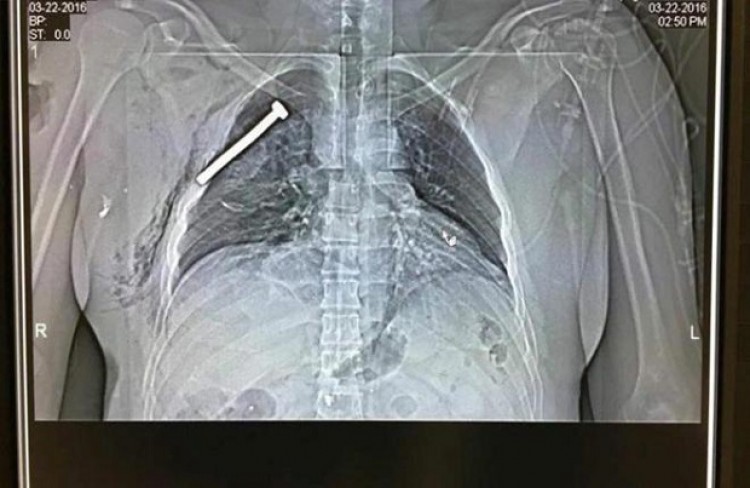

Todo apunta a que los terroristas habían rellenado los explosivos con tornillos para causar el mayor daño posible cuando activaron los detonadores, que llevaban ocultos bajo sus guantes.El diario La Libre Belgique difundió la radiografía de un herido en el aeropuerto donde puede verse un tornillo de considerable tamaño incrustado en uno de sus pulmones. El medio belga añade que se desconoce el estado del paciente, ingresado en un centro hospitalario al norte de la capital belga.Marc Decramer, administrador del hospital universitario Gasthuisberg de Lovaina, ratificó esa misma pista al señalar que <a href="http://www.primeraedicion.com.ar/nota/216824/al-menos-34-muertos-en-cadena-de-atentados-del-estado-islamico-en-br.html">la mayoría de las víctimas</a> que trataron allí presentaban heridas que indican que las bombas contenían tornillos.Y en una vivienda registrada por la policía en el distrito bruselense de Scharebeek fue hallado también "un artefacto explosivo con tornillos, entre otros elementos, así como productos químicos", según ha comunicado el fiscal general de Bélgica, Frédéric Van Leeuw.Fuente: diario El Mundo (España)LEA LOS DETALLES SOBRE EL ATENTADO HACIENDO <a href="http://www.primeraedicion.com.ar/nota/216824/al-menos-34-muertos-en-cadena-de-atentados-del-estado-islamico-en-br.html">CLICK AQUÍ</a> Y EN LA EDICIÓN IMPRESA DEL MIÉRCOLES 23 DE MARZO